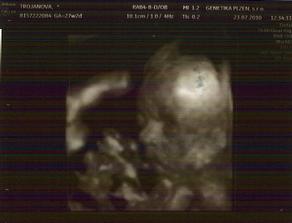

23.7.2010 jdeme na 3D ultrazvuk 🙂 - 27tt+2

3D ultrazvuk byl prostě bomba, všechno nám pan doktor zkontroloval

takže máme 34cm a 1,4kg a máme všechno co máme mít

pohlaví jsme si říct nakonec nenechali, tak se necháme překvapit a v říjnu uvidíme 🙂